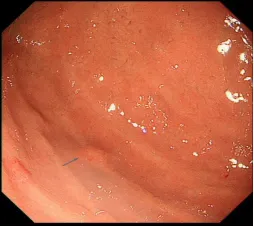

近日,UG环球国际附属第二医院消化内科门诊接诊了一位患者,在外院行普通胃镜检查提示胃粘膜下隆起,经人介绍患者来我院寻医诊治,张又莉副主任接诊后为该患者行小探头超声内镜检查,成功检出并定性诊断病灶。

左:普通胃镜;右:超声内镜